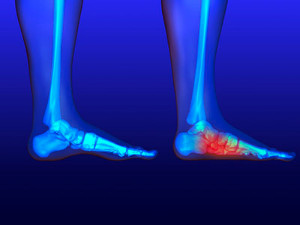

Stress fractures develop when a bone that’s constantly under stress eventually weakens. It typically occurs on the outside of the bone and happens due to repetitive motion. Many professional athletes and runners develop this condition, as overuse of the bones in the foot is common. The way the foot is structured may be another cause, as having flat feet or higher arches may be a contributing factor in developing stress fractures. When overdoing a specific activity, the risk is high for developing these fractures. There may not be physical signs and symptoms from the fracture, but when the activity resumes, pain is often felt. An x-ray is used to determine exactly where the fracture is. Recovery comes from resting the foot and being careful not to put stress on the bones. Occasionally a medical boot is worn to keep the fracture from worsening, in addition to engaging in physical therapy. Please seek the advice of a podiatrist if you feel you have a stress fracture in the foot or ankle.

Stress fractures develop when a bone that’s constantly under stress eventually weakens. It typically occurs on the outside of the bone and happens due to repetitive motion. Many professional athletes and runners develop this condition, as overuse of the bones in the foot is common. The way the foot is structured may be another cause, as having flat feet or higher arches may be a contributing factor in developing stress fractures. When overdoing a specific activity, the risk is high for developing these fractures. There may not be physical signs and symptoms from the fracture, but when the activity resumes, pain is often felt. An x-ray is used to determine exactly where the fracture is. Recovery comes from resting the foot and being careful not to put stress on the bones. Occasionally a medical boot is worn to keep the fracture from worsening, in addition to engaging in physical therapy. Please seek the advice of a podiatrist if you feel you have a stress fracture in the foot or ankle.

Activities where too much pressure is put on the feet can cause stress fractures. To learn more, contact one of our podiatrists from New Jersey Foot & Ankle Centers. Our doctors can provide the care you need to keep your pain free and on your feet.

Dealing with Stress Fractures of the Foot and Ankle

Stress fractures occur in the foot and ankle when muscles in these areas weaken from too much or too little use. The feet and ankles then lose support when walking or running from the impact of the ground. Since there is no protection, the bones receive the full impact of each step. Stress on the feet can cause cracks to form in the bones, thus creating stress fractures.

What Are Stress Fractures?

Stress fractures occur frequently in individuals whose daily activities cause great impact on the feet and ankles. Stress factors are most common among:

- Runners

- People affected with Osteoporosis

- Tennis or basketball players

- Gymnasts

- High impact workouts

Symptoms

Pain from the fractures occur in the area of the fractures and can be constant or intermittent. It will often cause sharp or dull pain with swelling and tenderness. Engaging in any kind of activity which involves high impact will aggravate pain.

If you have any questions please feel free to contact our office located in Oradell, NJ . We offer the newest diagnostic and treatment technologies for all your foot and ankle needs.